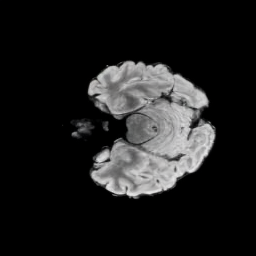

Motivated by this, we propose X-Diffusion, a novel architecture that learns on 3D volumetric data by utilizing view-dependent cross-sections. This approach allows for full MRI generation with high accuracy from a single MRI slice or multiple slices (see Figure 1). Unlike previous methods that treat MRI data as collections of 2D slices in standard planes (coronal, axial, sagittal) or rely heavily on frequency-domain data, X-Diffusion operates directly in the spatial domain and models MRI samples as complete 3D volumes during both training and inference. To our knowledge, X-Diffusion is the first method capable of producing detailed 3D MRIs from highly limited 2D input data, potentially accelerating MRI acquisition and reducing associated costs. It is important to note that the generated MRIs are not clinical replacements for true MRIs yet, but could provide a quick, affordable, and informative “pseudo-MRI” before conducting a full MRI examination.

The X-Diffusion model is trained with cross-sections from all different directions and all different depths , which allows it to generate the target from any arbitrary rotation and depth (see Figure 3). At inference, unrolled X-Diffusion is applied times with from an arbitrary orientation , and decoded with decoder to obtain the view-conditional volume . This volume is then rotated back by to the Canonical orientation to produce the final output MRI .

Multi-View MRI Volume Generation. One advantage of our cross-sectional diffusion is that it can learn and generate the volume from any arbitrary view direction (as in Equation 3). In training, this allows X-Diffusion to train on MRIs from all types of cross-sections, unlike the typically followed common 3 planes (coronal, sagittal, and axial) [18, 36, 24], which allows the model to generalize better. At inference, we leverage this power to generate volumes from different views predefined as equally distributed views around the around the azimuth horizontal rotations , where is the rotation matrix defined by rotating by degrees around the vertical axis (0,1,0). The final MRI volume output is then obtained by averaging the view-conditional volumes ( from Eq ((3))) at inference after rotating back to the canonical orientation of the output as follows. This multi-view aggregation is inspired by how multi-view discriminative methods learn a global representation by aggregating multiple views features[66, 26]. We show in Section 6.1 the utility of the volume averaging compared to a single volume.